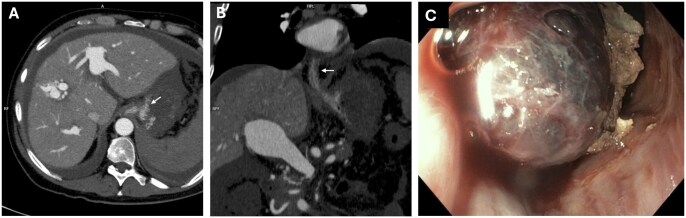

经颈静脉肝内门静脉-全身分流术(TIPS)是治疗门静脉高压(PH)并发症的有效方法。在这里,我们报告了一个复杂的病例,由于胃食管静脉曲张破裂引起的出血性休克,在PH的背景下,最初是由特发性的,可能是先天性的,高流量肝内动脉门静脉瘘(IAPFs)持续,然后是广泛的肠缺血。虽然iapf的闭塞有可能控制内脏动脉血液进入门静脉循环,但它无法控制PH相关出血,因此需要放置补补性TIPS。门静脉压力梯度在IAPFs闭塞后持续显著增加,表明独立的肝内成分导致ph。此外,肝脏组织学显示,长期IAPFs继发于肝实质的窦前/窦前阻塞反应,导致肝内ph的发作。基于这些原因,联合介入方法导致了难愈的门静脉高压出血的解决。避免弥漫性肠梗死的致命性发展。

Transjugular intra-hepatic porto-systemic shunt (TIPS) is a proven strategy for the management of portal hypertension (PH) complications. Here, we report on a complex case of haemorrhagic shock due to the rupture of gastro-oesophageal varices in the context of PH originally sustained by idiopathic, likely congenital, high-flow intrahepatic arterioportal fistulas (IAPFs) preceded by extensive bowel ischaemia. While the occlusion of the IAPFs potentially controlled the steal of arterial splanchnic blood into the portal circulation, it failed to manage PH related bleeding, necessitating the placement of a salvage TIPS. Porta-caval pressure gradient persisted markedly increased after IAPFs occlusion, indicating an independent intra-hepatic component causing PH. Moreover, hepatic histology demonstrated a pre-sinusoidal/sinusoidal barrage response of the hepatic parenchyma secondary to long-standing IAPFs, causing the onset of an intra-hepatic component of PH. For these reasons, the combined interventional approach led to resolution of the refractory portal hypertensive bleeding, avoiding fatal evolution of diffuse bowel infarction.